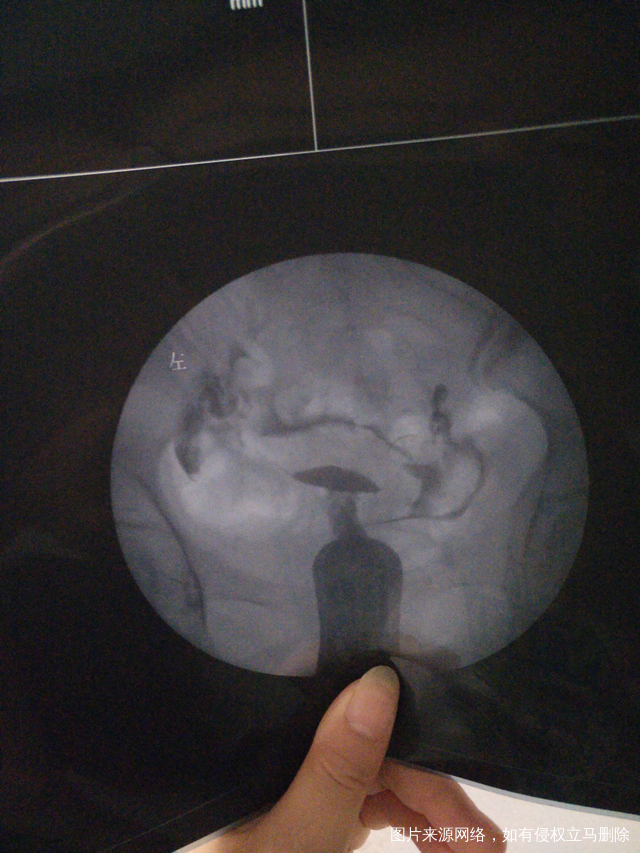

医生再帮我看看通吗她下面写双侧大该通还是就不通